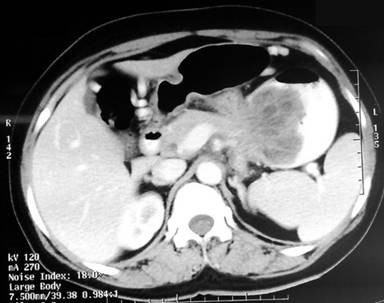

A 44-year-old female presented with lower abdominal colic since two months, associated with mucoid loose stools 10-15 times/day and weight loss of approximately 5 kg in two months. On examination, a firm mass was felt in the left upper quadrant moving with respiration. On further evaluation, she was found to be anemic with hemoglobin of 7.0 g/dL (reference range: 12-16 g/dL). Fecal occult blood was positive on two occasions. Colonoscopy revealed a large polypoidal growth near the splenic flexure of colon almost completely obstructing the lumen. Biopsy was suggestive of inflammatory polyp. Contrast enhanced computed tomography scan (Figure 1) showed an irregular enhancing mass lesion in the colon at the splenic flexure of colon. There was no evidence of significant lymphadenopathy or adjacent organ involvement. The differential diagnoses were adenomatous polyp of the colon or adenocarcinoma of the colon.

Figure 1. CECT of the abdomen revealed a polypoidal lesion in the splenic flexure of colon. |